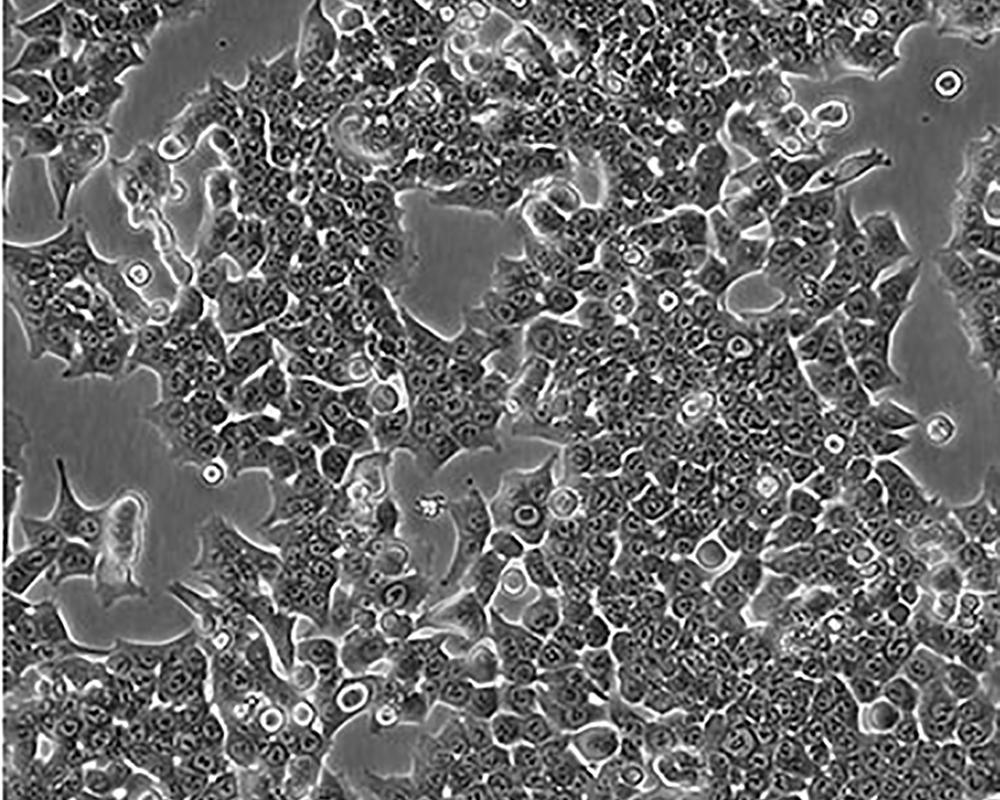

產(chǎn)品名稱(chēng) HCT 116

中文名稱(chēng) 人結(jié)直腸腺癌細(xì)胞

組織來(lái)源 結(jié)腸腺癌;男性

生長(zhǎng)特性 adherent

培養(yǎng)基 McCoy's 5A+10% FBS+1% P/S

形態(tài)特征 epithelial

細(xì)胞描述 The cells are positive for keratin by immunoperoxidase staining.HCT 116 cells are positive for transforming growth factor beta 1(TGF beta 1) and beta 2(TGF beta 2) expression.